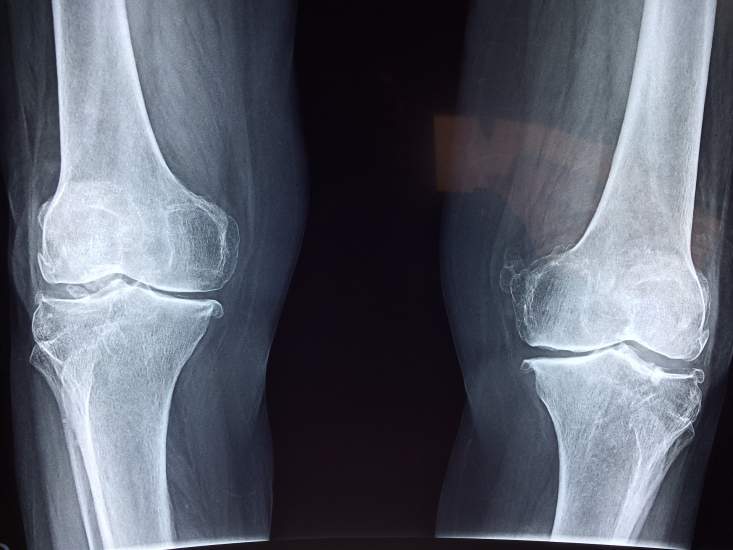

Sąnarių skausmai – viena dažniausių problemų, dėl kurios kreipiamasi į sveikatos specialistus, ypač keičiantis orams. Nors kiekvieno žmogaus organizmas į oro pokyčius reaguoja skirtingai, temperatūros, slėgio bei drėgmės pasikeitimai dažniausiai neigiamai paveikia sąnarių būklę. Nemalonūs pojūčiai kankina ne tik senjorus. Dėl fizinio aktyvumo stokos sąnarių problemos vis dažniau pasireiškia ir jaunimui.

Vaistininkė Jovita Juodsnukytė atkreipia dėmesį, kad oro pokyčiai sąnarius stipriausiai paveikia tiems, kurie yra patyrę traumų, bei vyresniems žmonėms, kuriuos kamuoja lėtiniai sąnarių uždegimai.